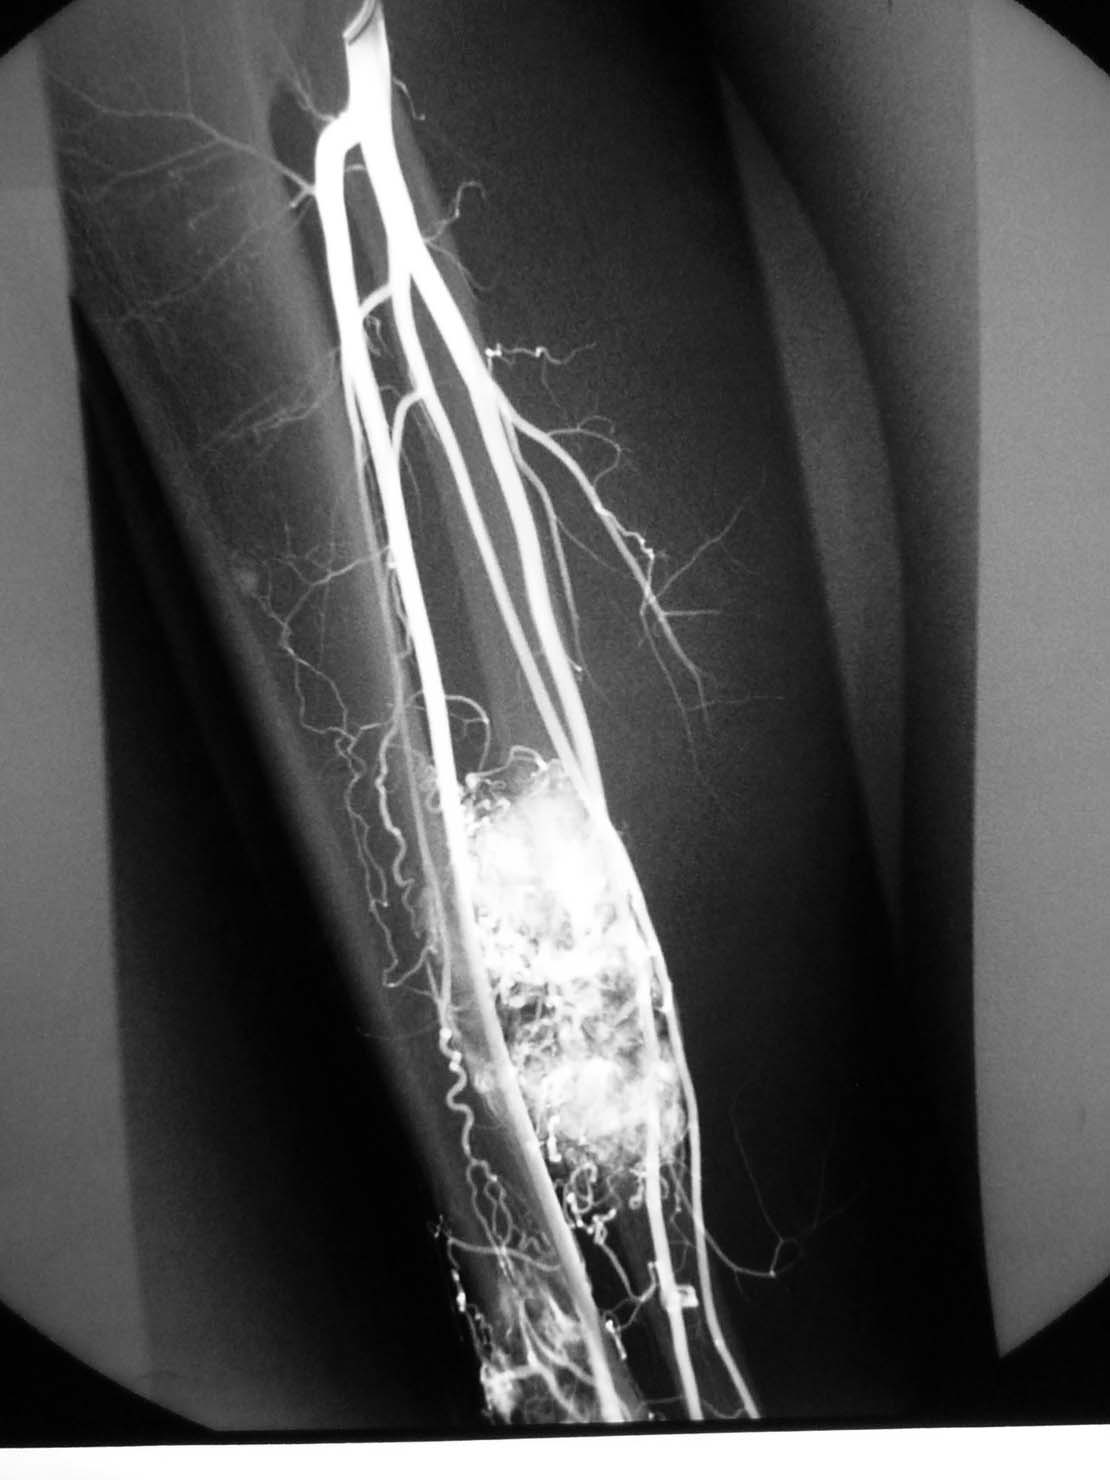

腺泡样软组织肉瘤

[emb14]

极为罕见,其组织来源不明。

起源于肢体软组织者称腺泡状软组织肉瘤,原发于骨内者,称骨腺泡状肉瘤。

本病大多发生于股部、臀部及小腿深侧肌群,上肢和其他部位少见。

x线平片:圆形或卵圆形软组织肿块影,基底部与病骨相连。

肿瘤内可见斑点状或细小结节状钙化。

骨质破坏大多表现为溶骨性地图状或虫噬性破坏,并常伴有层状骨膜反应。

mr检查:t1和t2加权像均显示肿瘤组织呈分叶状高信号强度,并见肿瘤内有低信号间隔。